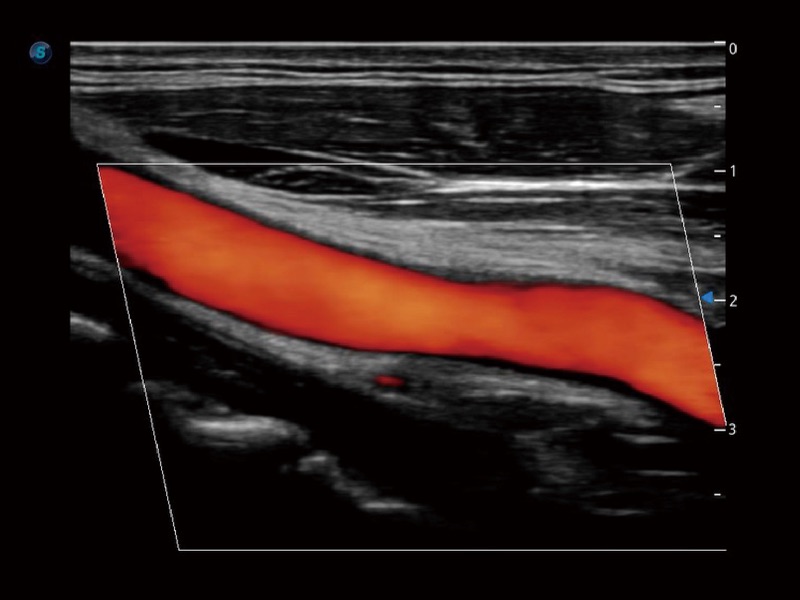

• SR Flow 高分辨率血流成像技术

高分辨率血流成像技术提高了对低速血流信号的检测能力。在提高空间分辨率的同时,也克服了血流外溢现象,为用户提供更加真实的血流动力学信息。

• 血管内中膜自动测量 Auto IMT

血管内中膜的厚度值是预测心血管疾病风险的重要指标,Auto IMT可以实现血管近场和远场内中膜厚度的自动测量,为临床提供快捷有效的诊断工具。